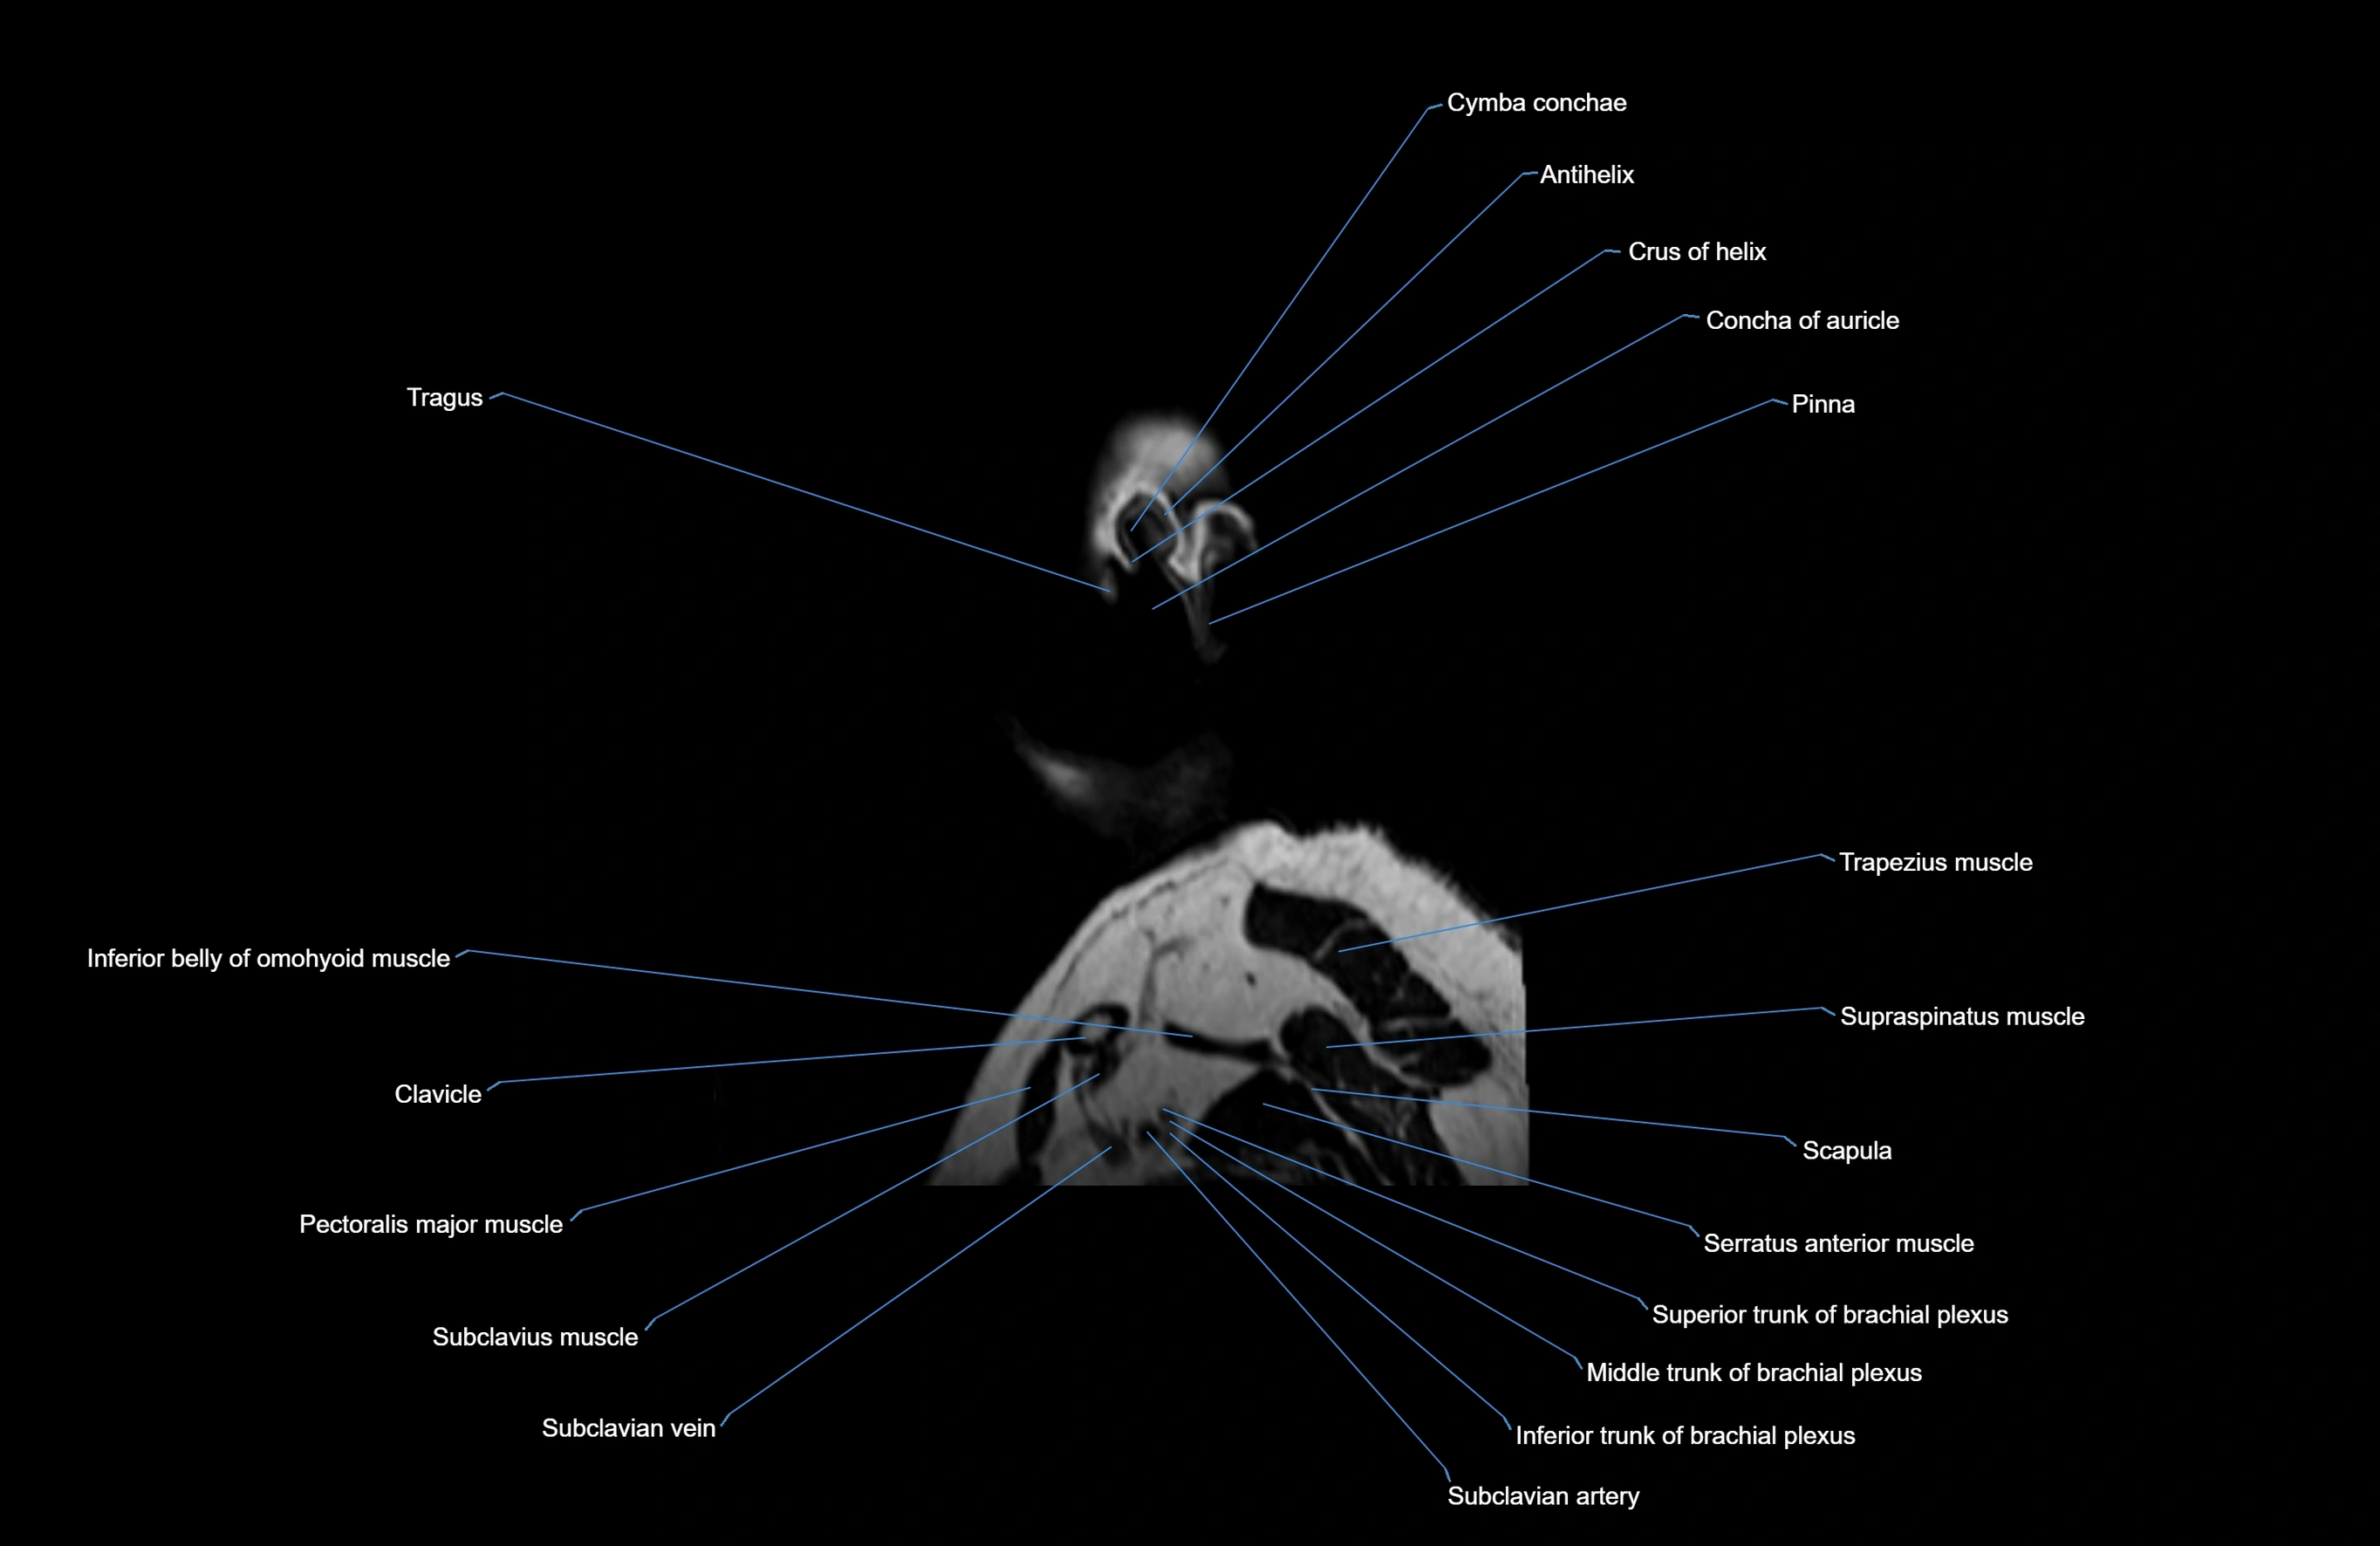

MRI images